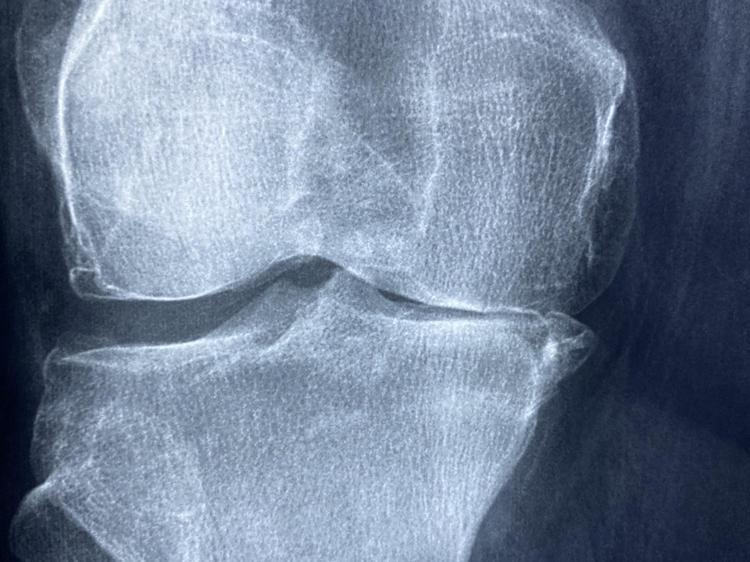

膝关节活动时发出弹响是很常见的情况,医学上叫关节弹响。有研究发现,大概60%的健康人都有生理性弹响,但如果弹响同时伴随疼痛或肿胀,往往意味着可能存在病理问题。膝关节的稳定和功能依赖韧带、滑液、肌肉等多个结构的协同,出现异常弹响的原因主要和以下三个机制有关:

膝关节的稳定靠四组主要韧带共同维持,就像机械装置的铰链一样,得各个部件协同工作才行。如果其中某条韧带松弛或损伤,关节面的接触方式就会改变,进而导致半月板和软骨异常摩擦,时间长了可能加快关节老化。

关节腔里有少量滑液,负责润滑关节。如果韧带损伤引发了滑膜炎,滑液分泌会变多。通过影像学检查发现,关节活动时腔内压力变化会让气体快速释放,从而产生响声——这种类似“关节腔内压力释放”的现象,具体机制还在研究中。

现在医学上会用磁共振成像等技术评估韧带损伤,治疗方案包括保守治疗(比如康复训练、物理治疗)和手术干预,具体选哪种要看损伤程度。近年还有生物制剂用于关节修复的研究,但临床疗效还需要更多验证。